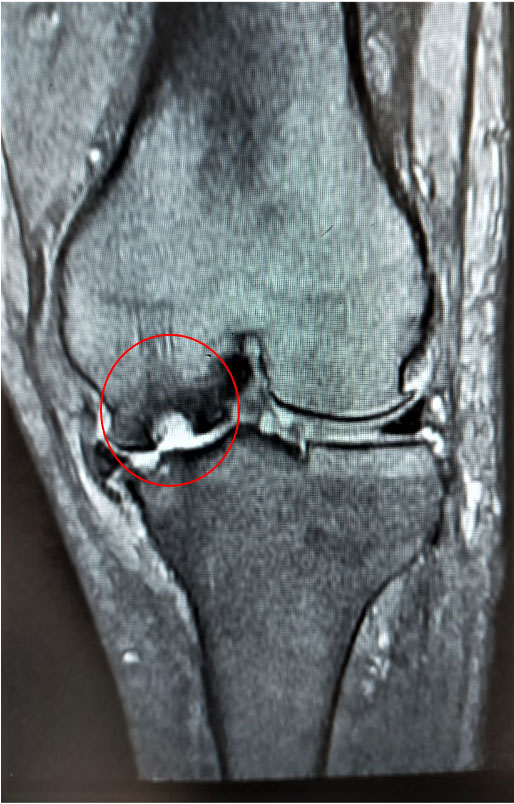

大腿骨顆部は体重を支えるのに重要で、過度なストレスが加わり壊死に陥ることがあります。原因としてステロイド投与や半月板損傷後などに脆弱性骨折(軽微な外傷により軟骨下骨に微小骨折を生じる)が起こり壊死に至るとされています。安静にしていても痛みが出たり、夜間寝ている間に痛みが出ることもあります。

大腿骨顆部骨壊死

MRI